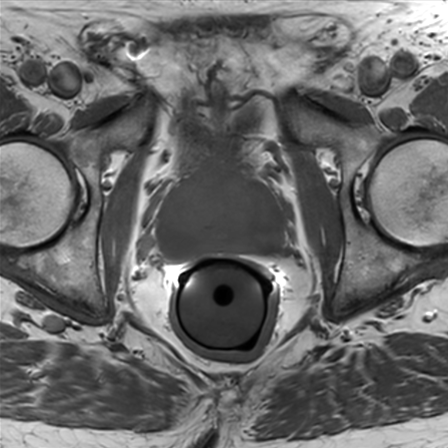

Prostate imaging with dS Endo + dS Torso coil

• Coil

• Clinical Application